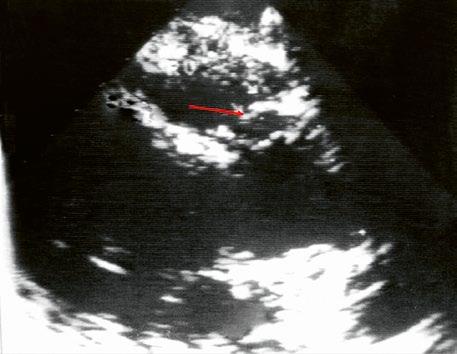

Malé restriktivní defekty komorového septa (Rogerova choroba) nevedou ke vzniku plicní hypertenze ani k srdečnímu selhání. Mají typickou vysokorychlostní dopplerovskou křivku (Obr. 45.35), odpovídající vysokém gradientu mezi levou a pravou komorou v systole a poslechovému nálezu hlučného systolického šelestu.

Obr. 45.35 CW záznam vysokorychlostního dopple rovského toku z levé do pravé komory malým restriktivním defektem komorového septa. Vysoký gradient na komorovém defektu vylučuje vysoký tlak v pravé komoře při plicní hypertenzi nebo při těžké stenóze plicnice.